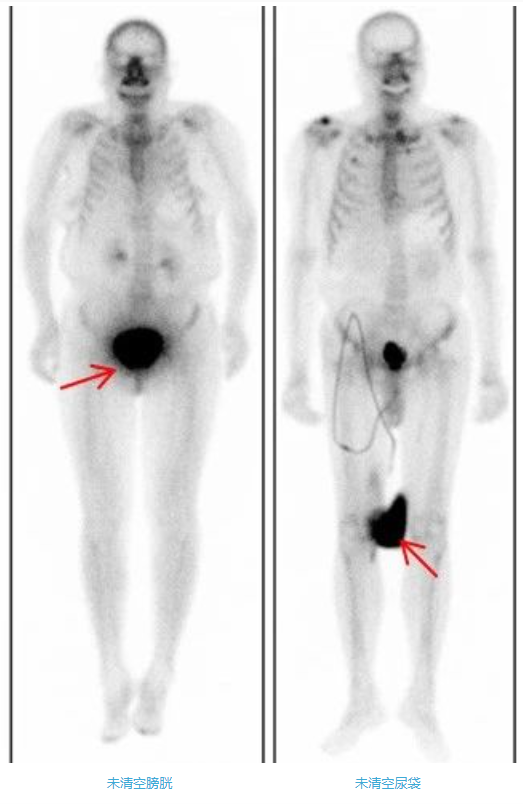

4、多喝水,清空膀胱

注射骨顯像劑后2-5小時(shí),50%-60%顯像劑沉積在骨骼中,剩余的顯像劑或潴留在肌肉或通過尿液排出體外。為了提高骨骼圖像質(zhì)量,注射骨顯像劑后,需要注射后多飲水(一般500ml-1000ml,受檢者如無明顯不適可增大飲水量)、多排尿。大量小便潴留在膀胱內(nèi),會(huì)影響骨盆區(qū)骨骼的判讀,所以掃描前要清空膀胱。排尿時(shí)須避免尿液污染皮膚和衣物。一旦污染了衣物,形成放射性偽影,會(huì)影響圖像質(zhì)量和結(jié)果判讀,因此需更換衣物或清洗污染部位后重新進(jìn)行掃描。如果患者有尿袋,檢查前需要清空尿袋;同樣注意避免污染皮膚和衣物。